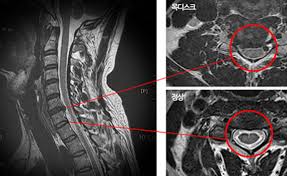

목디스크는 경추와 흉추 부위에서 발생할 수 있으며, 이러한 디스크의 변화는 주로 디스크의 손상된 부분이 주변 신경을 압박하거나 자극함으로써 다양한 증상을 유발합니다.

목디스크는 하중이 한 부위에 집중되어 경추 사이에 있는 추간판이 파열되고 내부의 수핵이 변위될 수 있는 상태를 가리킵니다.

이러한 상태는 공식적으로는 경추 추간판 탈출증으로 알려져 있으며, 목의 추간판이 손상되어 통증과 불편을 초래할 수 있습니다. 목디스크는 일상 활동에서의 부적절한 자세나 무리한 운동, 또는 직업적 요인으로 발생할 수 있습니다.